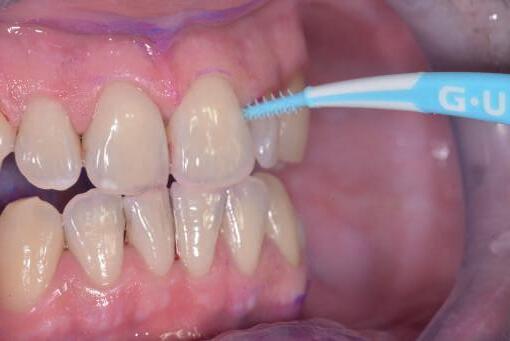

Si presenta alla nostra attenzione un paziente maschio, 35 anni, in apparente salute sistemica, fumatore, con la richiesta di controllare delle white spots, una leggera sensibilità e la richiesta di migliorare la luminosità del suo sorriso. Viene compilato e firmato il consenso informato. Il paziente viene motivato ad più efficace controllo del biofilm batterico e attraverso la condivisione dell’immagine clinica della topografia del biofilm batterico, (T.B.M.) scegliamo lo scovolino in gomma GUM Soft-picks (Sunstar) e lo sollecitiamo all’uso efficace degli spazi sovracrestali e allo spazzolamento in maniera delicata ma efficace della lingua. Sottoponiamo il paziente alla terapia parodontale non chirurgica con ablatore Comby touch (MECTRON) in modalità soft-mode per contenere la sua sensibilità. Valutiamo la sensibilità e modifichiamo i suoi stili di vita di igiene orale, di igiene alimentare e chiediamo di smettere di fumare. Il paziente riferisce di non essere disposto a rinunciare al fumo e chiediamo di ridurre il rischio di patologie e di discromie

da tabagismo passando all’uso dei dispositivi a tabacco riscaldato. Successivamente rileviamo il colore, con spettrofotometro, e con scala-colori Vita e documentiamo fotograficamente la condizione clinica presente.

Il colore rilevato è A2. Sottoponiamo il paziente ad uno sbiancamento pro-

fessionale con un principio attivo PAP (acido ftalimidoperossicaproico) che presenta il vantaggio di non sollecitare la sensibilità, pur mantenendo l’aspettativa di un risultato efficace nell’ottenere la luminosità del sorriso. Lo sbiancante ad uso professionale BRILLIANT LUMINA (Coltene), risulta essere per l’operatore di facile applicazione: ven-

gono protette le gengive con la diga liquida fotopolimerizzata, e si mescola il gel sbiancante lasciando cadere nel vasetto contenente 2 ml di gel, 3 gocce di liquido attivatore. Si ottiene il gel sbiancante di una consistenza ideale per una applicazione sulle superfici dentali sicura e pratica durante l’apposizione. Vengono eseguiti 4 step da 15 minuti.